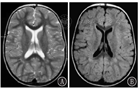

3.6 早产儿脑损伤[15,16,17]早产儿脑损伤的主要原因是围生期缺氧缺血,经典病理形式是脑室周围-脑室内出血(periventricular-intraventricular hemorrhage,PVL-IVH)和PVL。根据Paneth将早产儿脑损伤分为脑白质损伤(brain white matter damage,WMD)、脑非实质区出血、脑其他部位(小脑、基底核和脑干等)损伤。其中WMD又分为囊性、非囊性和弥散性脑白质病变3种(图15)。

下图列出的是每个脑损伤类别中有代表性的个体婴儿[15](轴位T2加权MRI扫描显示)(图16)。

图16

每个脑损伤类别中有代表性的个体婴儿轴位T2加权磁共振成像结果 A:足月婴儿(对照);B:极早产的婴儿,无脑损伤,存在折叠减少,解剖结构正常;C:极早产儿,Ⅲ/Ⅳ级IVH,可见脑室内和脑室周围出血;D:极早产儿伴IVH和出血后脑积水,侧脑室扩张;E:极早产儿伴有囊性脑室旁白质软化症

Figure 16

Representative individual infant axial T2 weighted magnetic resonance imaging results in each brain injury category A:full-term infant;B:very preterm infant without brain injury,note dolichocephalic shape and decreased folding but otherwise normal anatomy;C:very preterm infant with grade Ⅲ/Ⅳ IVH,note presence of intra-and periventricular hemorrhage;D:very preterm infant with IVH and post-hemorrhagic hydrocephalus requiring neurosurgical intervention,note dilated lateral ventricles;E:very preterm infant with cystic periventricular leukomalacia